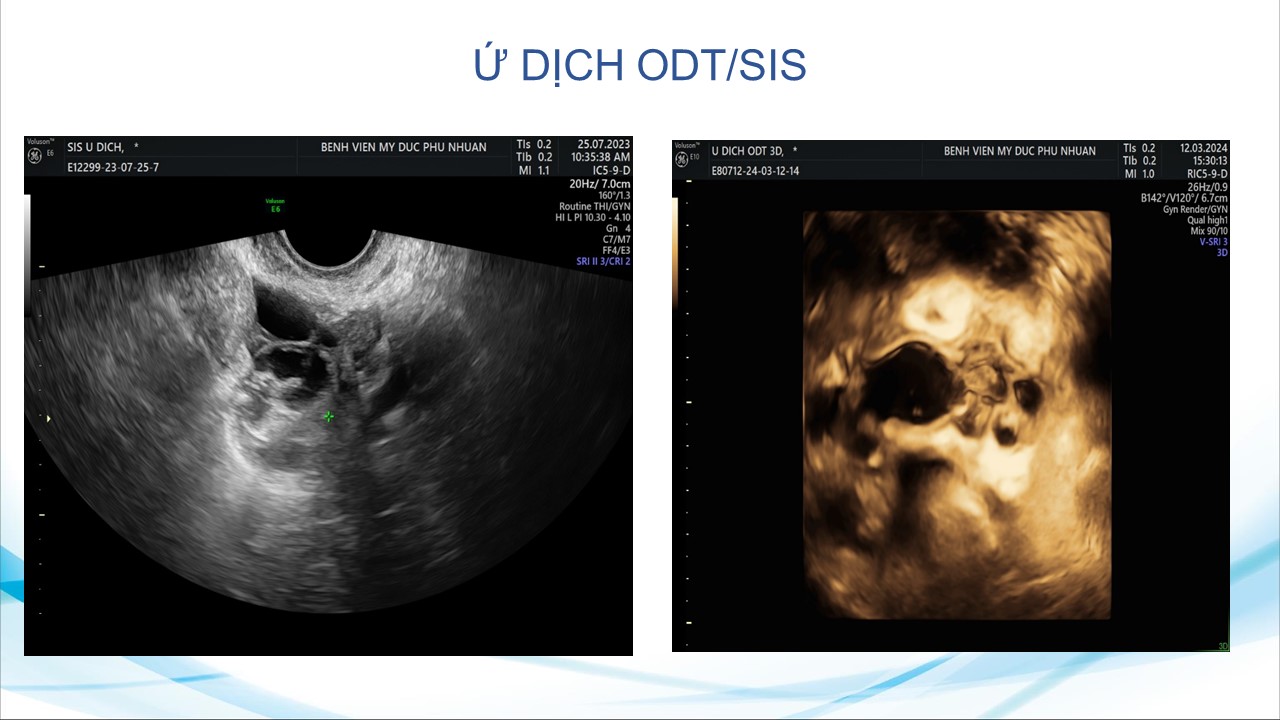

Siêu âm sử dụng chật tương phản trong phụ khoa

BS. CKI Phạm Thị Phương Anh - Bệnh viện Mỹ Đức